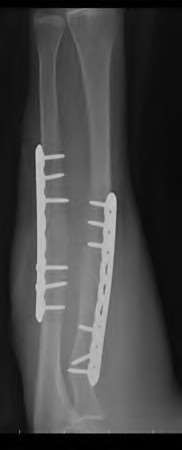

Question 19:

A 28-year-old male sustains a closed comminuted tibial shaft fracture. Two hours post-injury, he develops severe leg pain unyielding to narcotics. His blood pressure is 120/80 mmHg. Intracompartmental pressure monitoring is performed. Based on current guidelines, which measurement dictates an emergent 4-compartment fasciotomy?

Correct Answer: Delta pressure (Diastolic BP - Compartment Pressure) < 30 mmHg

Explanation:

Acute compartment syndrome is classically defined by tissue hypoperfusion. The absolute compartment pressure is less reliable than the differential pressure (Delta P). A Delta P (Diastolic Blood Pressure minus Compartment Pressure) of less than 30 mmHg is an absolute indication for emergency fasciotomy, as capillary perfusion gradient is lost when tissue pressure approaches the diastolic pressure.